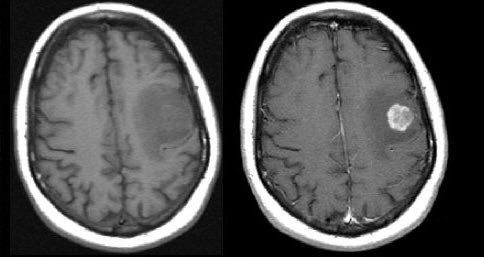

2. T1+gadolinium*: "Where is the BBB disrupted?"

**always compare T1+gad sequences to pure T1 without contrast (if also bright on pure T1, then BBB not necessarily disrupted)**